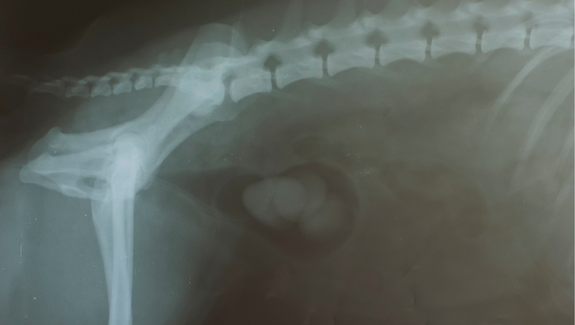

August 26, 2022Many pet parents are shocked to see their dog’s X-rays reveal large stones in their dog’s bladder. Most commonly, dogs with bladder stones need to go outside every hour or have accidents in the house. Identifying this condition as early as possible is crucial since a urinary obstruction may be life-threatening and require immediate emergency treatment.

It is important to confirm the diagnosis of bladder stones with an X-ray or ultrasound, as these symptoms can also be associated with other diseases affecting the urinary tract (infections and tumors, for example).